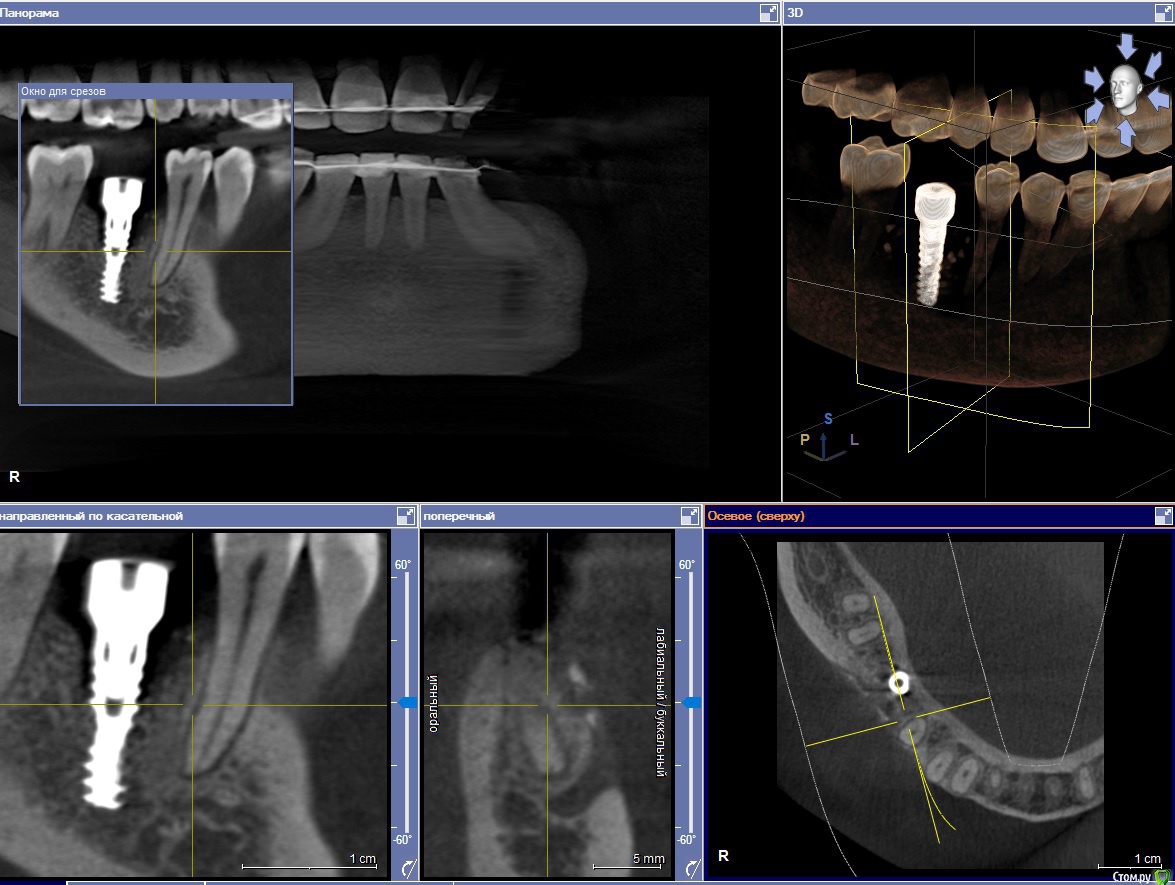

akburan Опубликовано 8 февраля, 2017 Поделиться Опубликовано 8 февраля, 2017 Установили имплант 3 мес. назад. Имплант прижился.Одновременно с имплантацией провели синус-лифтинг. До операций имела также место рецессия десны. Но через 3 недели после установки и подсадки костн. материала десна опустилась еще ниже в области импланта и 3.5 зуба, из-за чего мне кажется, что внедрили мало костного материала. С этой жалобой обращалась к хирургу неоднократно, на что он отвечал что все хорошо и десна со временем САМА восстановится. В данный момент уже сняли слепки для дальнейшего протезирования, но мне состояние десны категорически не нравится и я хочу что-то с этим сделать. Можно ли восстановить десну в обл. импланта? Возможно ли не извлекать при этом имплант? Поможет ли лоскутная операция в том смысле, что прирастет ли лоскут к импланту? Ссылка на комментарий

DrNice Опубликовано 9 февраля, 2017 Поделиться Опубликовано 9 февраля, 2017 А не могли бы Вы подробно описать проблему с костью?И что с ней надо делать? Меня смущает участок просветления на снимке, в области трех верхних витков импланта. Ссылка на комментарий

Oscar Опубликовано 13 марта, 2017 Поделиться Опубликовано 13 марта, 2017 Объем десны можно добавить, но основная проблема резорбция костной ткани в верхней трети импланта, кстати что за система? Израиль? Ссылка на комментарий